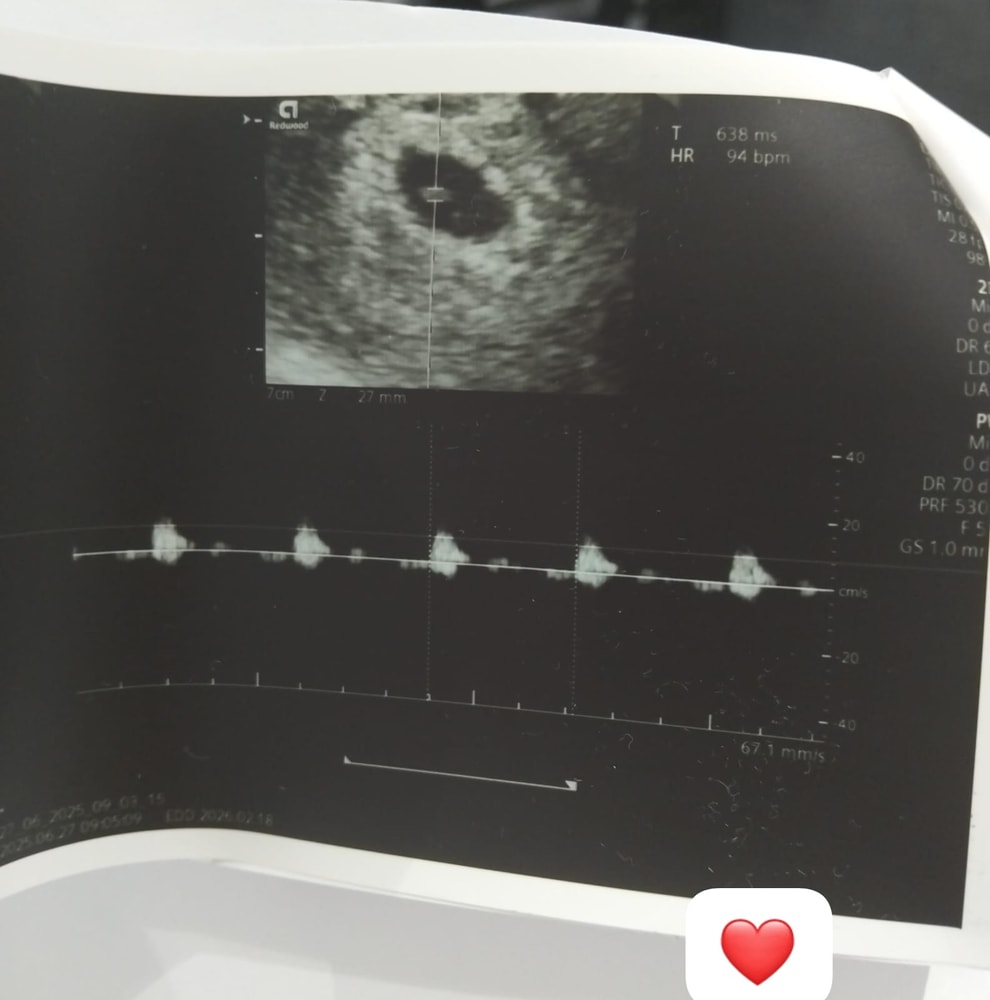

Только что с УЗИ через неделю. Сейчас кроха 4мм, послушали СЕРДЕЧКО.

ЧСС 93-94, срок 6 недель. Врачу хотелось бы ЧСС больше 100.

Но может быть пока нормой, позже разгонится.